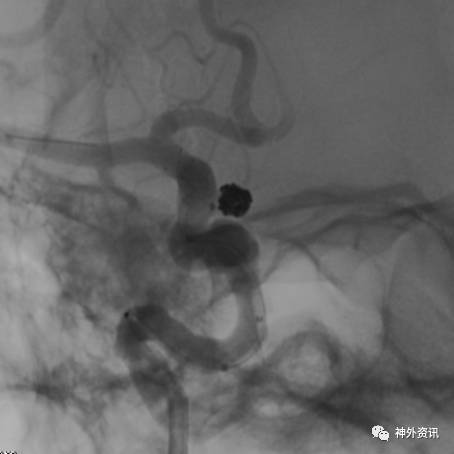

猪尾塑形

猪尾左行和右行

微导管尾端向下直立,头端向前弯曲时,头端相对左偏为左行,右偏为右行。

指向下方的颈内动脉眼段或床突段动脉瘤(颈动脉窝动脉瘤)

指向下方的颈内动脉后交通段或脉络膜段动脉瘤

(1)左侧颈内动脉-猪尾左行

(2)右侧颈内动脉-猪尾右行